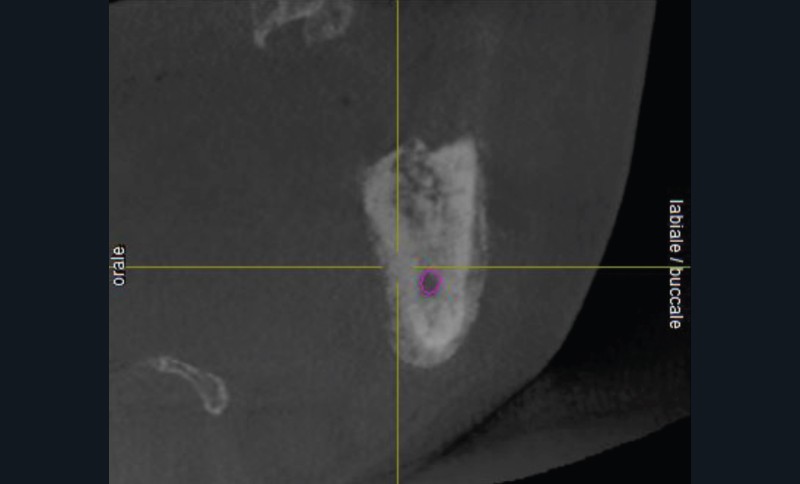

L’examen radiologique (scanner ou tomographie a faisceau conique) est très évocateur. Il montre un épaississement périosté avec « aspect mixte » de l’os médullaire et des « perforations corticales ».

L’ostéomyélite passe par plusieurs stades au cours de son évolution. Au début, les zones d’ostéolyse et de sclérose sont invisibles radiologiquement…